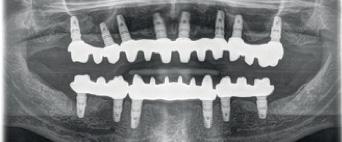

During daily practice, it is very common to face situations where the implant has to be placed lingually due to normal resorption (Fig. 1) of the buccal plate after the extraction. But, at the same time, it is not necessary to perform bone grafting procedures. The result of this scenario is to increase the stress on the implant-bone complex when we use rigid materials like conventional ceramics (Fig. 2).

For this daily practice situation, the combination of rigid and resilient materials against the antagonist, allows the stress to the implant-bone complex to be reduced (Fig. 3,4).

Another common situation is a full mouth restoration over implant. It is well known that the big issue is chipping and delimitation of the ceramics, due to the high forces applied in the patient with dental implants.

In regards to this problem, the combination of rigid materials to support the connectors and resilient materials to absorb the shock and, at the same time, allow easy fixation, make the use of resin based blocks the logical choice for this kind of restoration. (Fig. 6,7 and 8)

In this case, a patient presented with extremely atrophic bone in the mandible, with four short implants placed between the dental nerve foramen (Fig, 10a,10b). These were milled out of a BRILLIANT Crios disc either as single tooth units or bridges and cemented on the thimble struc-ture (Fig. 15-17). Using BRILLIANT Crios instead of prefabricated teeth, we can increase the strength of the restoration, have good aesthetics and keep the weight low for this kind of prosthesis.